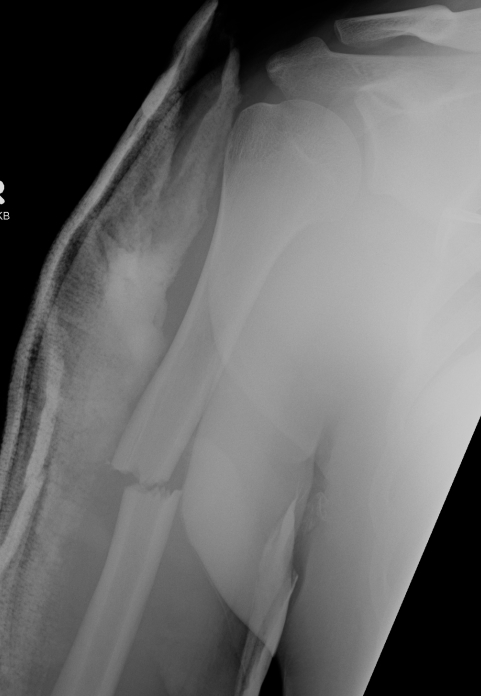

Holstein Lewis fracture

Holstein Lewis fractureHolstein Lewis

Holstein-Lewis JBJS Am 1963

- series of 7 oblique distal third fractures with radial nerve injury

- all were treated operatively

- nerve in fracture gap in 2 / impaled in 1 / severed in 2 / contused +/- in callus in 2

- advised against attempted closed reduction

- risk of contusing nerve between fragments

- advised early open reduction through anterolateral approach

- the radial nerve is closely assoicated with the fracture site and the fracture spike